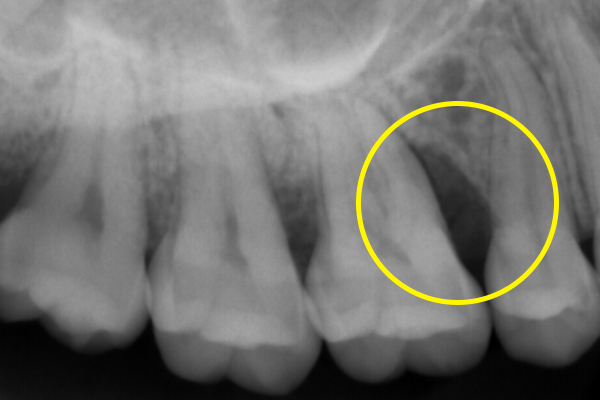

また、日本国内で一般的に行われる歯周病における抜歯の判断基準は、比較的すぐに「抜歯」と判断する傾向があります。歯周病専門医として、世界基準に沿った抜歯の判断をし、残せると判断すれば、全力を尽くして歯を残す治療を行います。

どうしても、抜歯が必要な場合も、抜歯する歯は最小限に抑え、噛む機能を最大限に維持していきます。